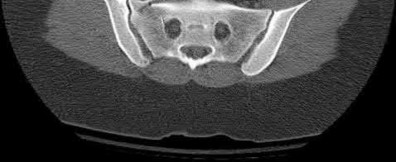

During head-on motor vehicle collisions occurring at highway speeds, airbag-protected individuals have a decreased rate (as compared to non-airbag protected individuals) of all of the following EXCEPT:

Corrent answer: 4

The referenced study by Loo et al. studied the interaction between airbags/seatbelts and mechanism of the crash (ie. front vs. side impact) and the injury patterns in these patients. They found that in frontal crashes, airbags reduced Glasgow Coma Scale severity in brain injury, facial fracture, shock, thoracoabdominal injuries and the need for extrication. Frontal airbags also had a protective effect on lower extremity fractures, but had no significant protective effect on pelvic fractures.